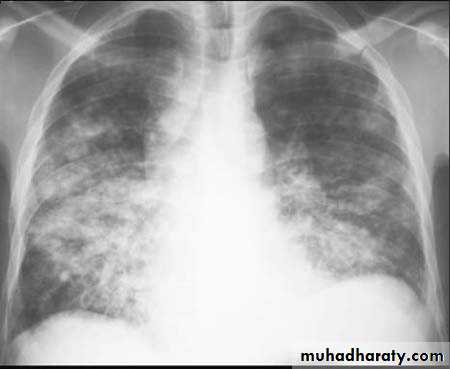

Bronchopneumonia

Bronchopneumonia (also sometimes known as lobular pneumonia 1) is a radiological pattern associated with suppurative peribronchiolar inflammation and subsequent patchy consolidation of one or more secondary lobules of a lung in response to a bacterial pneumonia.Lobar lung collapse

Multi-focal consolidation

Multiple areas of opacity seen throughout the lung most often is due to bronchopneumonia, starting from bronchi and spreading outwards. Usually ill defined with peripheral distribution. Neoplasms such as a primary malignancy or metastasis can also cause this picture.